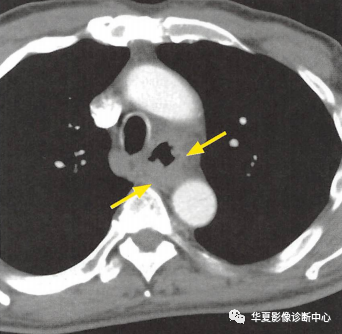

(上图:增强CT食管壁不规则增厚)

①食管壁改变:食管壁全周环形或局部不规则增厚,相应平面管腔变窄或消失,呈肿块样改变;

②食管周围脂肪间隙模糊、消失:提示食管癌向外侵犯;

③周围组织器官受累:多为气管和支气管,常形成食管-气管瘘,其次可侵犯心包膜、左心房和主动脉等;

④转移:以纵隔、肺门及颈部淋巴结转移多见,也可逆行性转移至上腹部淋巴结,少见肺转移。CT增强扫描可见瘤体轻度强化。较大瘤体呈不均匀强化,常合并低密度的坏死灶,较小瘤体强化均匀。